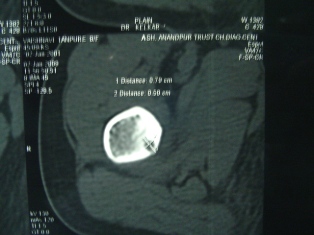

The child will complain of severe pain in the bone or near joint at night which is relieved by analgesic (combiflam). The pain is so severe that the child will wake up at night and cry and will stop only after pain medication is given. This will not be related to activity and will happen on a daily basis. It is a benign lesion. Radiograph will show a nidus surrounded by sclerotic bone. CT scan may be required for diagnosis. Surgical excision of nidus is indicated and it gives immediate relief. The patient will have no pain from the next day of surgery. Radio frequency ablation of lesion is also being done in select centers for specific location.